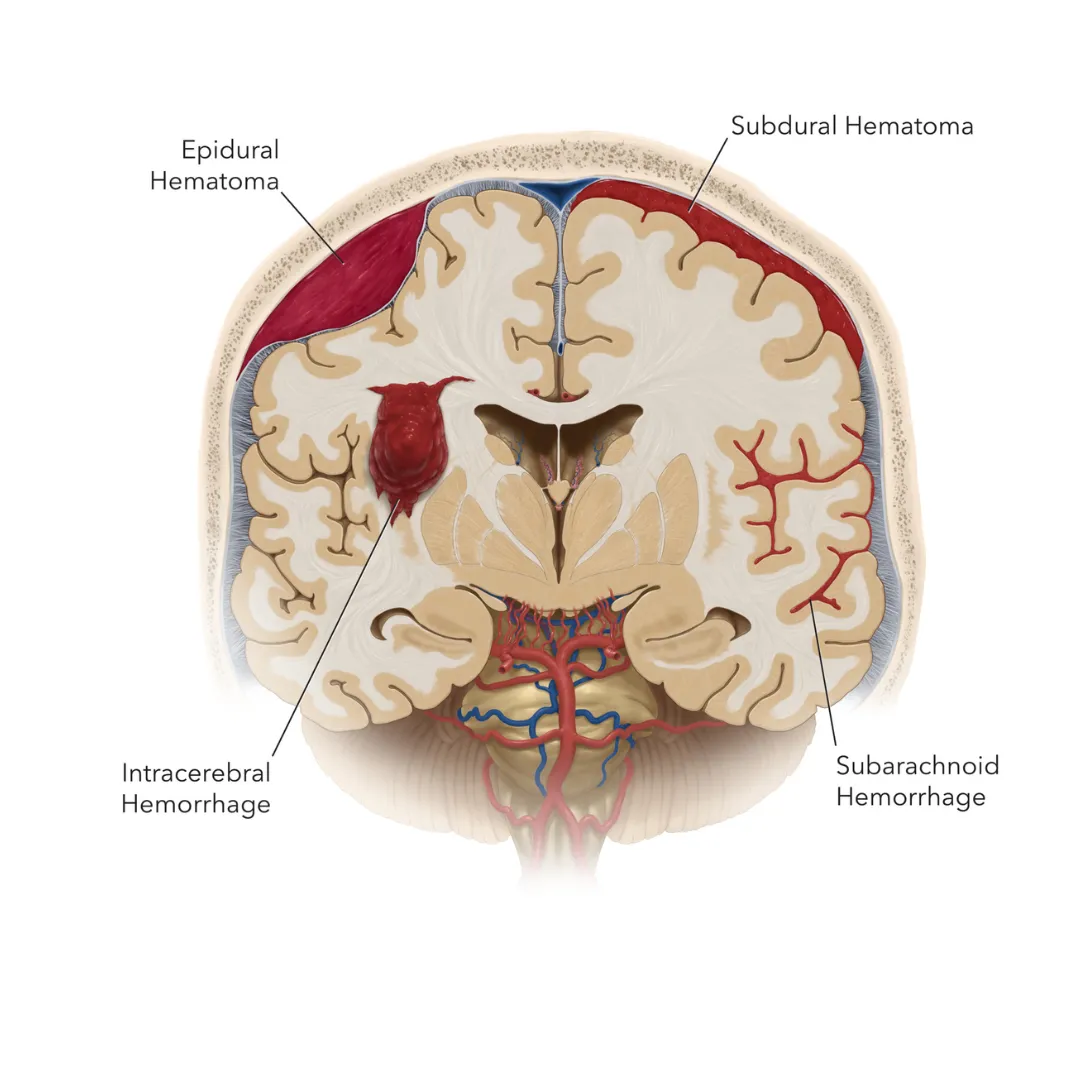

Critical Care

Critical Care

Hematoma Evacuation

Immediate surgical intervention for epidural and subdural hematomas to prevent life-threatening brain compression.